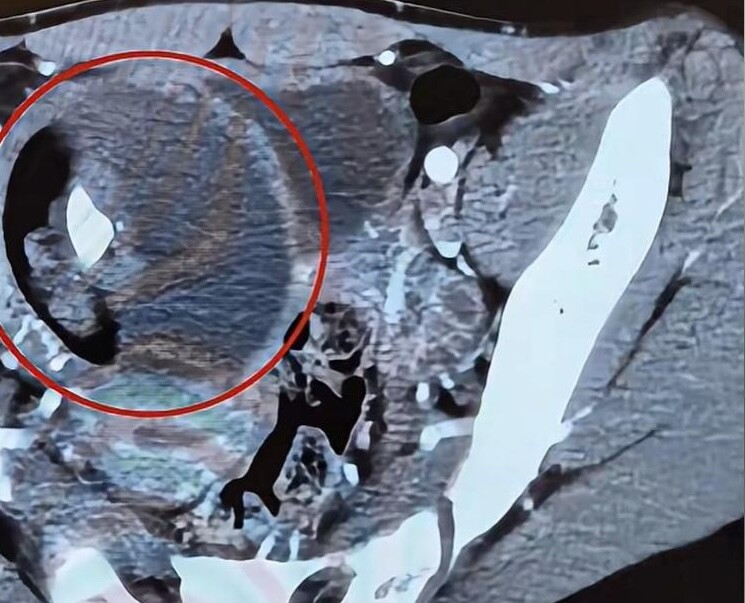

Ngay lập tức, người mẹ đưa Xiaoxin đến bệnh viện để kiểm tra. Sau các xét nghiệm, bác sĩ kết luận rằng Xiaoxin bị u quái thai. Tin này khiến mẹ đứa trẻ như chết lặng, suýt ngã xuống đất. Chị nhớ đến chữ "胎" (thai nhi) trong tên con gái, và nghi ngờ rằng có thể Xiaoxin đang mang thai. Nhưng đứa trẻ vẫn về nhà mỗi tối, vậy điều gì khiến con mang thai? Người mẹ hoảng loạn nghĩ liệu có phải con gái mình đã bị cưỡng hiếp, hoặc gặp chuyện gì nghiêm trọng khi từ trường trở về mà không dám kể cho mẹ.

Bác sĩ nhanh chóng trấn an chị, giải thích rằng khối u quái thai không phải do mang thai gây ra, mà là do một số tế bào mầm phát triển thành tóc, răng, xương và các mô khác, giống như một thai nhi, nên được gọi là "u quái". May mắn là khối u này không ác tính, và có thể được loại bỏ bằng phẫu thuật.

Theo bác sĩ, vị trí khối u của con gái chị tương đối thuận lợi, giúp cho ca phẫu thuật dễ dàng hơn. Ông cho biết bệnh viện đã từng gặp nhiều khối u ở não, và đó là những ca phẫu thuật khó khăn hơn rất nhiều. Xiaoxin thật may mắn khi được phát hiện sớm. Nghe bác sĩ phân tích, người mẹ cảm thấy nhẹ nhõm hơn, ngay lập tức sắp xếp cho con gái nhập viện để chuẩn bị cho ca phẫu thuật thành công.

Căn bệnh u quái thai ở trẻ nhỏ, hay còn gọi là teratoma, là một loại khối u hình thành từ các tế bào gốc trong quá trình phát triển thai nhi. Khối u này có thể xuất hiện ở nhiều vị trí khác nhau trên cơ thể, nhưng thường gặp nhất là ở vùng xương cụt, buồng trứng hoặc tinh hoàn. Điều đặc biệt về u quái thai là nó có thể chứa nhiều loại mô khác nhau, như tóc, da, và thậm chí là răng, khiến cho nó trở nên khác biệt so với các loại khối u khác.

Việc chẩn đoán u quái thai thường được thực hiện thông qua siêu âm, giúp xác định vị trí và kích thước của khối u. Trong nhiều trường hợp, bác sĩ có thể yêu cầu thực hiện MRI hoặc CT scan để có cái nhìn rõ hơn về cấu trúc của khối u và các mô xung quanh.